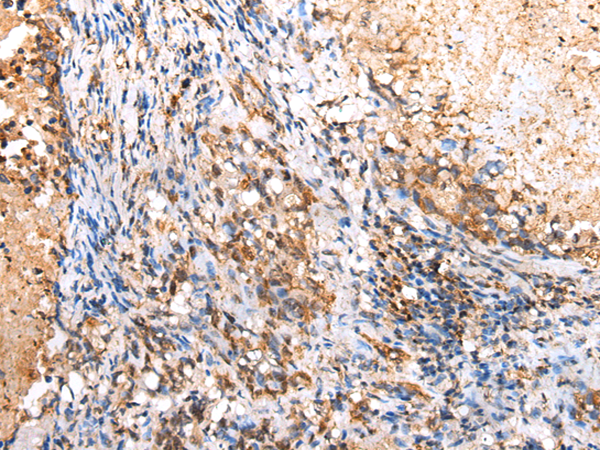

ELISA, IHC |

IHC positive control: |

Human lung cancer |

IHC Recommend dilution: |

25-100 |